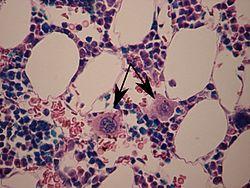

Two megakaryocytes in bone marrow, marked with arrows. | |